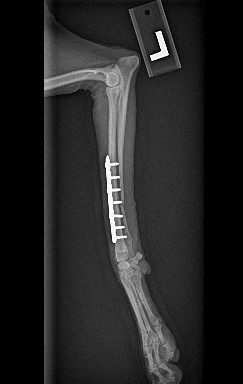

ADVANCED VETERINARY ORTHOPEDIC SERVICES

Our world-class, board-certified veterinary surgeons are dedicated to providing the most advanced canine orthopedic veterinary surgery and musculoskeletal assessment to ensure your beloved pet receives the most appropriate and comprehensive veterinary treatment available.